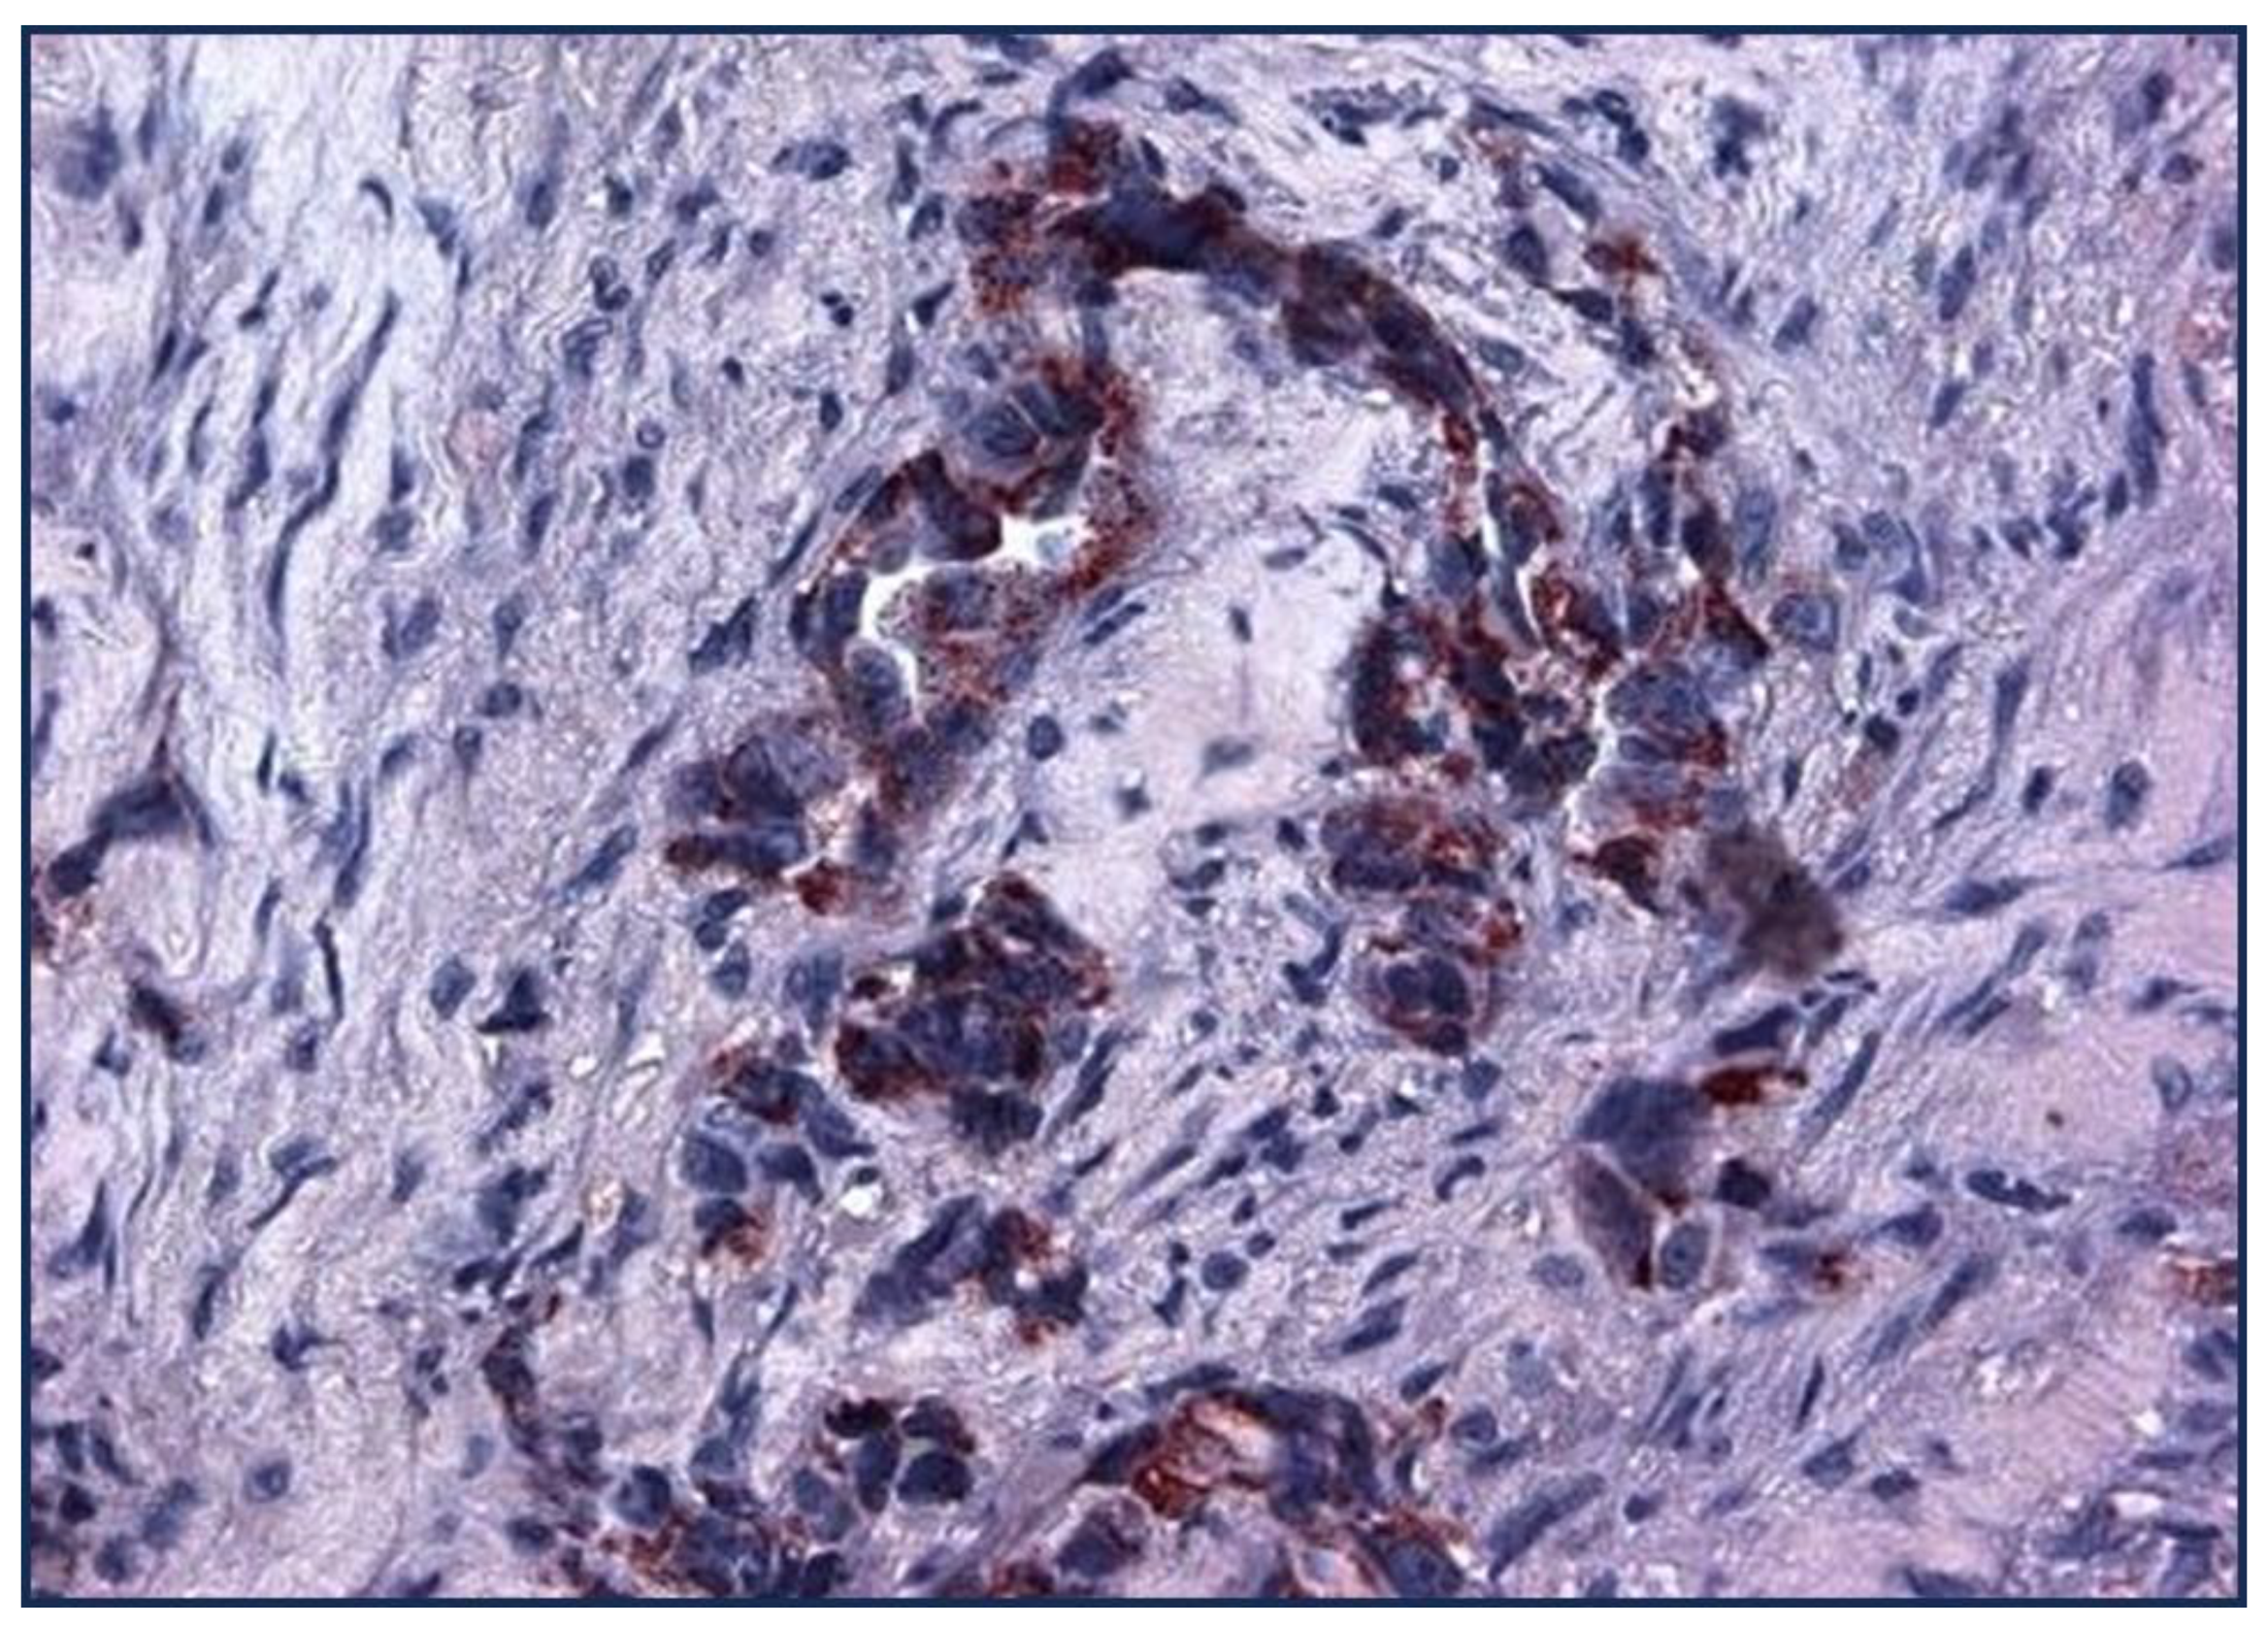

| Cancer Type | Adnab- 9(p87) |

TTF1(Clones) | NE Marker |

%p63/p40 | CK7 (NRecc) |

|---|---|---|---|---|---|

| Lepidic/BA | 67 | N/A | N/A | ||

| AdenoCa | 32 | 80(muc10-15) | N/A | 20-30 | 94-100 |

| Squamous | 6 | N/A | 5-77mean25% | ||

| Large Cell | 0 | 41 (9-85) | 92 | ||

| Small Cell | 22 | 79-100 | |||

| NSCLC | 15 | 10-20 | 68 | ||

| AdenoSquamous | 27 | N/A | 99 | ||

| Papillary | 74 | N/A | |||